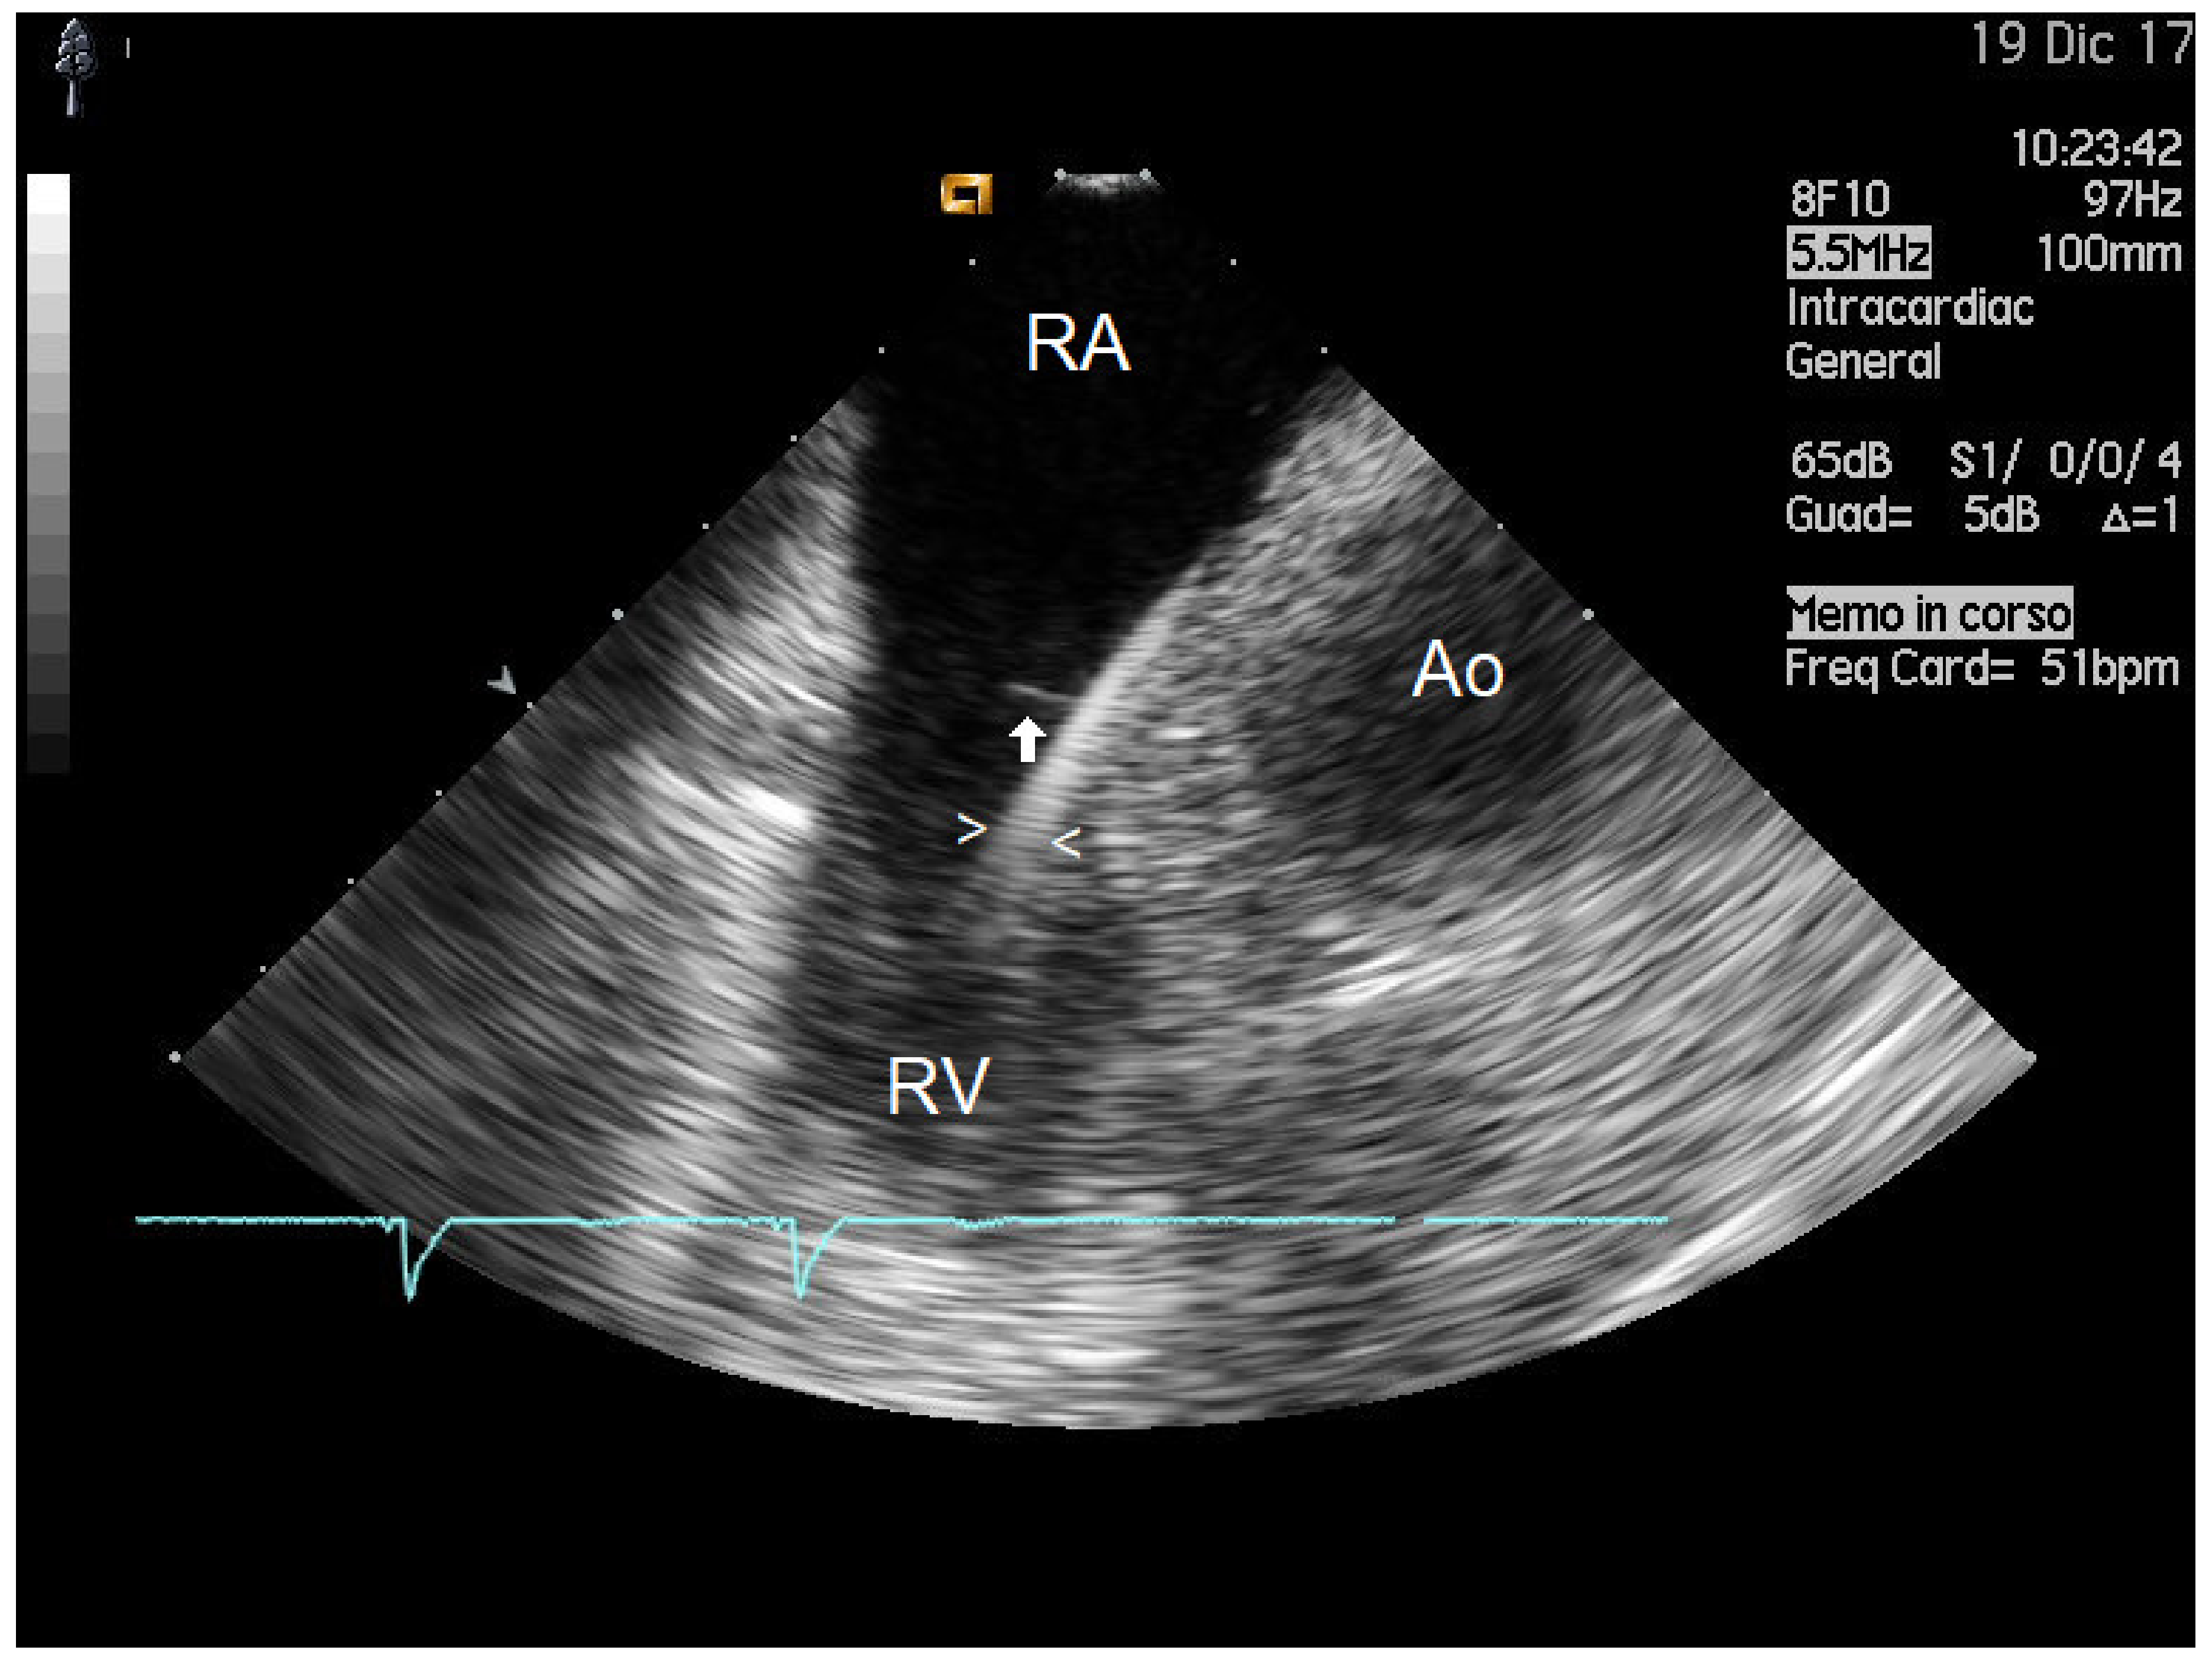

2.1. Mass Features and Associations

4.2. Intracardiac Echocardiography